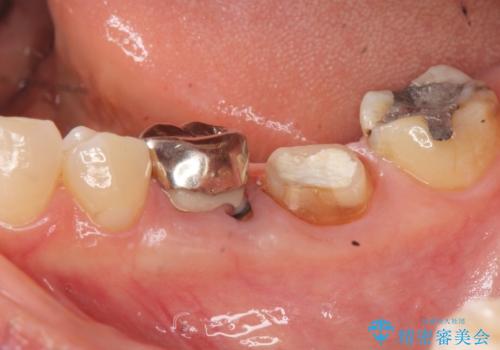

- 大人になってからも残っていた乳歯が揺れ始め、抜歯を覚悟しインプラント治療を希望して来院されました。

X線写真より、乳歯は抜歯が必要な状態でインプラントは小臼歯の埋伏により難しい状況であったのでブリッジによる補綴を選択しました。

ブリッジ治療の予知性を高めるために、虫歯の徹底的な除去に加え縁上歯質を確保するための歯周外科手術、マイクロスコープを用いた精密根管治療を行う治療計画としました。